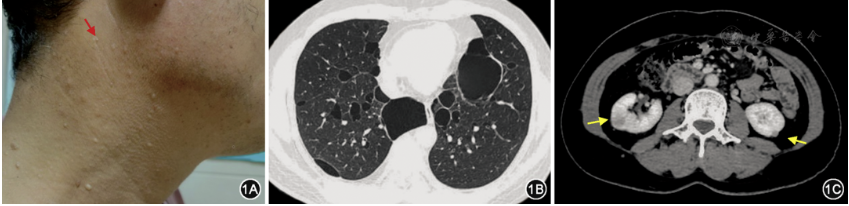

1. 肺部囊状病变:254例(99.2%)患者胸部CT观察到肺部囊状病变,其中248例(97.6%)患者病变位于双肺;大量囊状病变患者174例(68.5%),中量61例(24%),少量19例(7.5%);237例(93.3%)患者均为下叶分布为主;158例(62.2%)患者肺部囊状病变主要分布于纵隔旁,96例(37.8%)为胸膜下(表1)。综上,BHD患者胸部CT主要表现为双肺多发、大小不一囊状病变,主要分布于肺下叶和纵隔旁、胸膜下(图1)。北京、合肥、广州各中心患者肺部囊状病变发生率分别为100%(76/76)、98.6%(139/141)、100%(39/39),差异无统计学意义(χ2=1.64,P=0.440)。

图1 伯特-霍格-杜布综合征患者临床表现 1A. 患者颈部多发、肤色小丘疹(红色箭头),病理提示纤维毛囊瘤;1B. 胸部CT表现为双肺囊状病变,薄壁,大小不等,下叶分布为主,叶间裂、纵隔旁及胸膜下多见;1C. 肾脏增强CT表现为右肾中极及左肾下极类圆形软组织影(黄色箭头),边界清晰,密度均匀,动脉期明显强化,病理提示透明细胞癌

3. 皮肤病变:143例(55.9%)患者存在皮肤病变,其中仅22例进行皮肤病变活检,病理检查证实其中9例纤维毛囊瘤,2例毛盘瘤,5例表皮样囊肿,6例其他病变(表1)。除2例皮肤病变分布于躯干,其余141例(98.6%)均分布于面颈部(图1)。存在皮肤病变患者年龄19~76(45.9±11.7)岁,多见于30~50岁患者(图2)。北京、合肥、广州各中心皮肤病变检出率分别为48.7%(37/76)、72.3%(102/141)、10.3%(4/39),差异有统计学意义(χ2=50.01,P<0.001)。

4. 肾脏肿瘤:232例患者接受了肾脏影像学检测(包括超声162例、CT 60例、MRI 10例),其中10例(4.3%)发现肾肿瘤,包括肾细胞癌6例,肾血管平滑肌脂肪瘤4例。在6例肾细胞癌患者中,有3例嫌色性肾细胞癌、2例嗜酸性肾细胞癌、1例透明细胞性肾细胞癌(表1)。诊断肾肿瘤年龄为36~72(54±12)岁。北京、合肥、广州各中心肾肿瘤发生率分别为0、7.1%(10/141)、0,差异无统计学意义(χ2=5.11,P=0.078)。